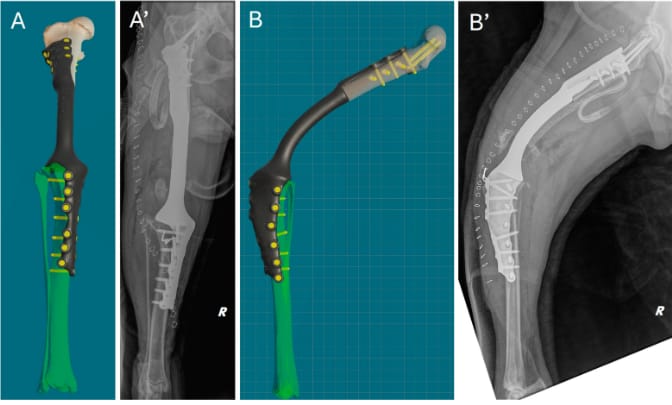

Comparison of virtual surgical planning and postoperative radiographs. (A,A’) Cranial view. (B,B’) Lateral view.

A preoperative CT scan was used for virtual surgical planning (VSP), enabling the design of patient-specific cutting guides (PSGs) and a titanium endoprosthesis (PSE). Surgery involved tumor resection via ostectomy, prosthetic implantation, and stifle arthrodesis. Postoperative care included pain management, antibiotics, and rehabilitation. Follow-ups were conducted at 3, 6, 12, and 18 months.

The PSG and PSE fit precisely, reducing intraoperative time and complications. The dog bore weight within 48 hours and exhibited stable mobility at follow-ups. No infection, limb misalignment, or tumor recurrence was observed up to 18 months post-surgery. The case highlights the efficacy of 3D-printed implants in maintaining limb function and quality of life.